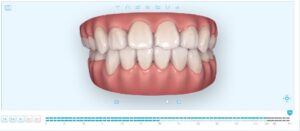

まずは初診時の写真を見て下さい。

【初診時】

まだ、矯正治療中ですが現在の写真を以下に示します。

【現在の状態】